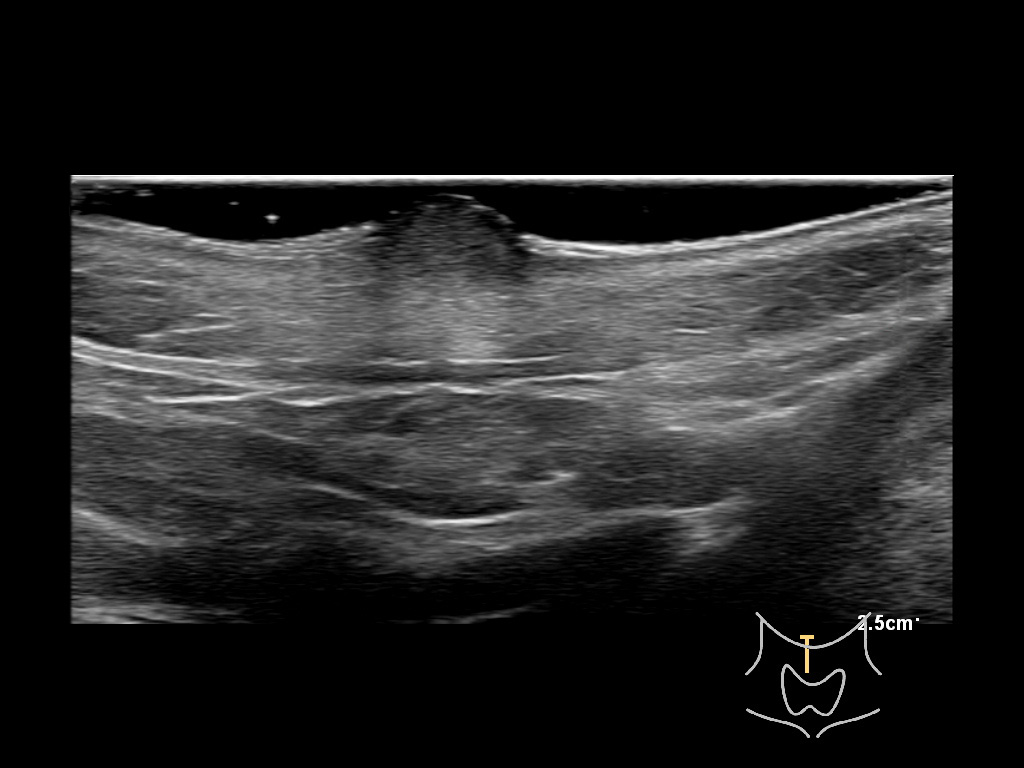

With ultrasound signs of inflammation can be visualized. Edema can be seen as a hyperechoic appearance of the subcutaneous fat, sometimes separated by hypoechoic fluid filled area’s, known as cobblestone appearance. Increased vascularization (hypervascularity) can be seen on colour Doppler. An abscess will appear as a fluid collection appearing as an irregular hypoechoic area with heterogeneous internal echoes and a thickened wall. Posterior acoustic enhancement can be present, and there is vascularity around but not within the mass. Under ultrasound guidance, abscesses can be managed by needle aspirations (18G) under antibiotic cover.

Study the first image to recognize the different layers. If you are sure about the layers, swipe to the second image to view the answer (if applicable).